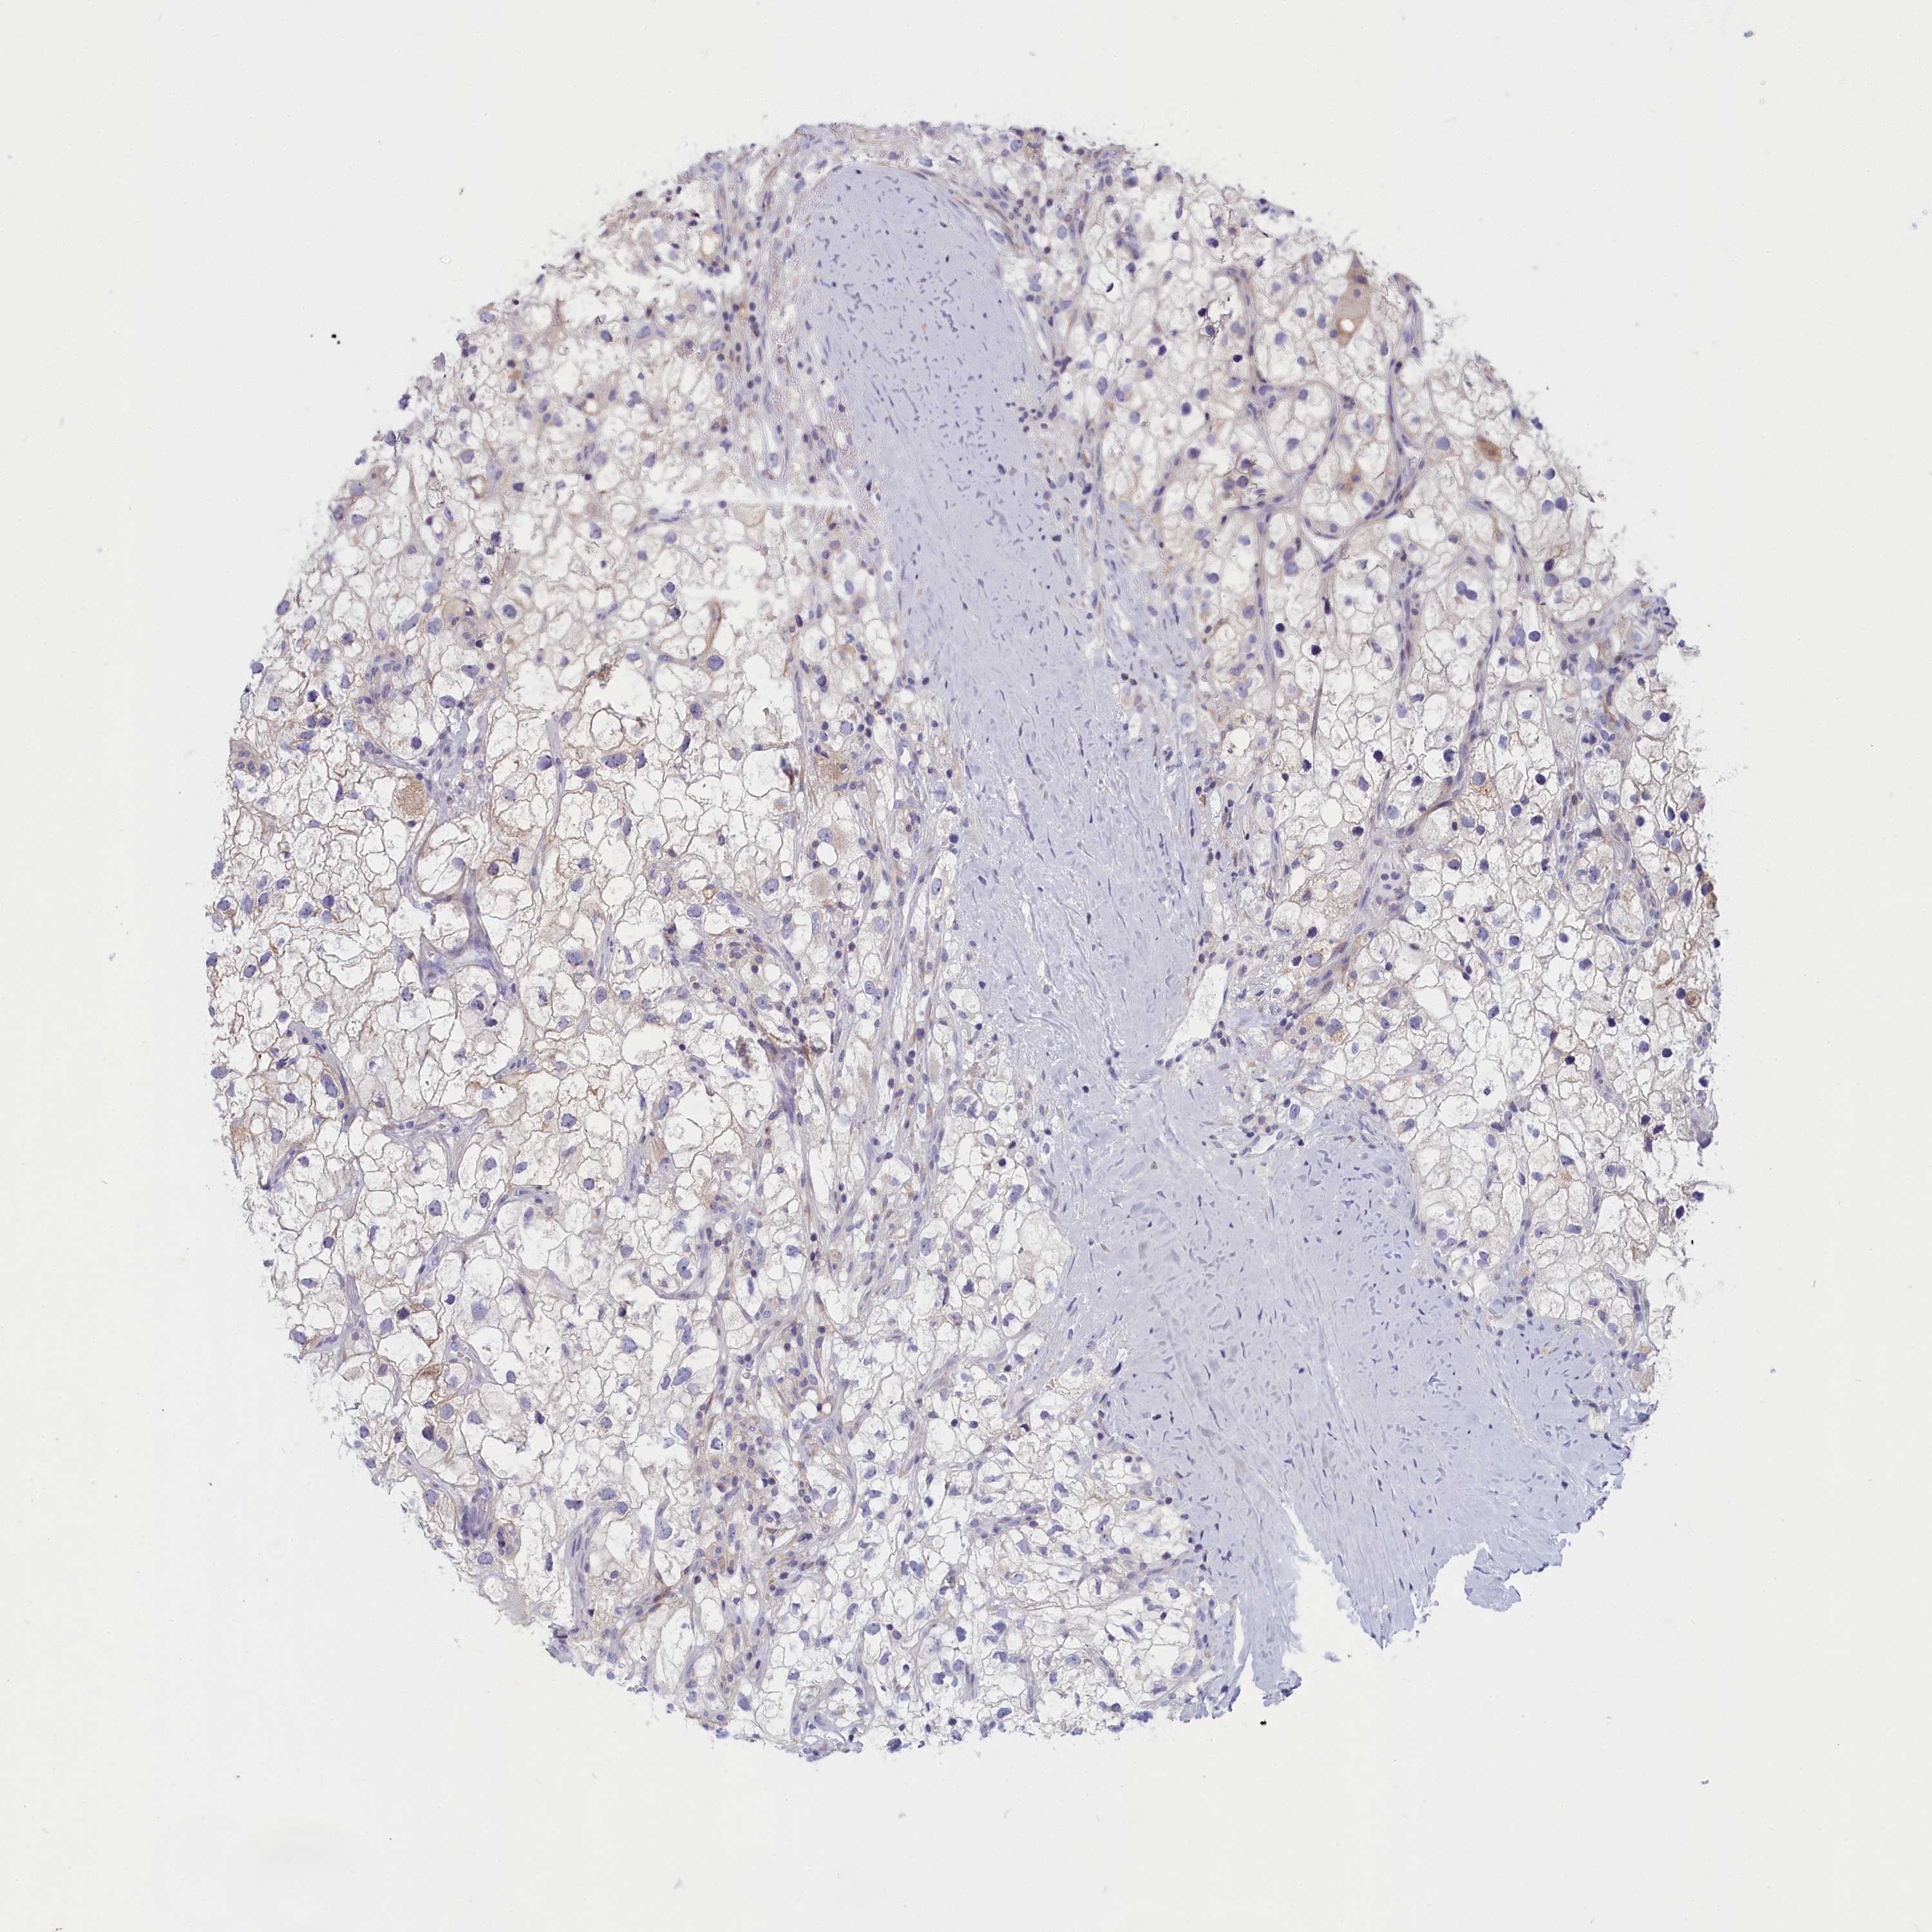

TCGA RNA samplesi

RNA-seq data is reported as average FPKM (number Fragments Per Kilobase of exon per Million reads), generated by the The Cancer Genome Atlas (TCGA) .

Normal distribution across the dataset is visualized with box plots, shown as median and 25th and 75th percentiles. Points are displayed as outliers if they are above or below 1.5 times the interquartile range. FPKM values of the individual samples are presented next to the box plot.

Average pTPM 14.6

Number of samples 100